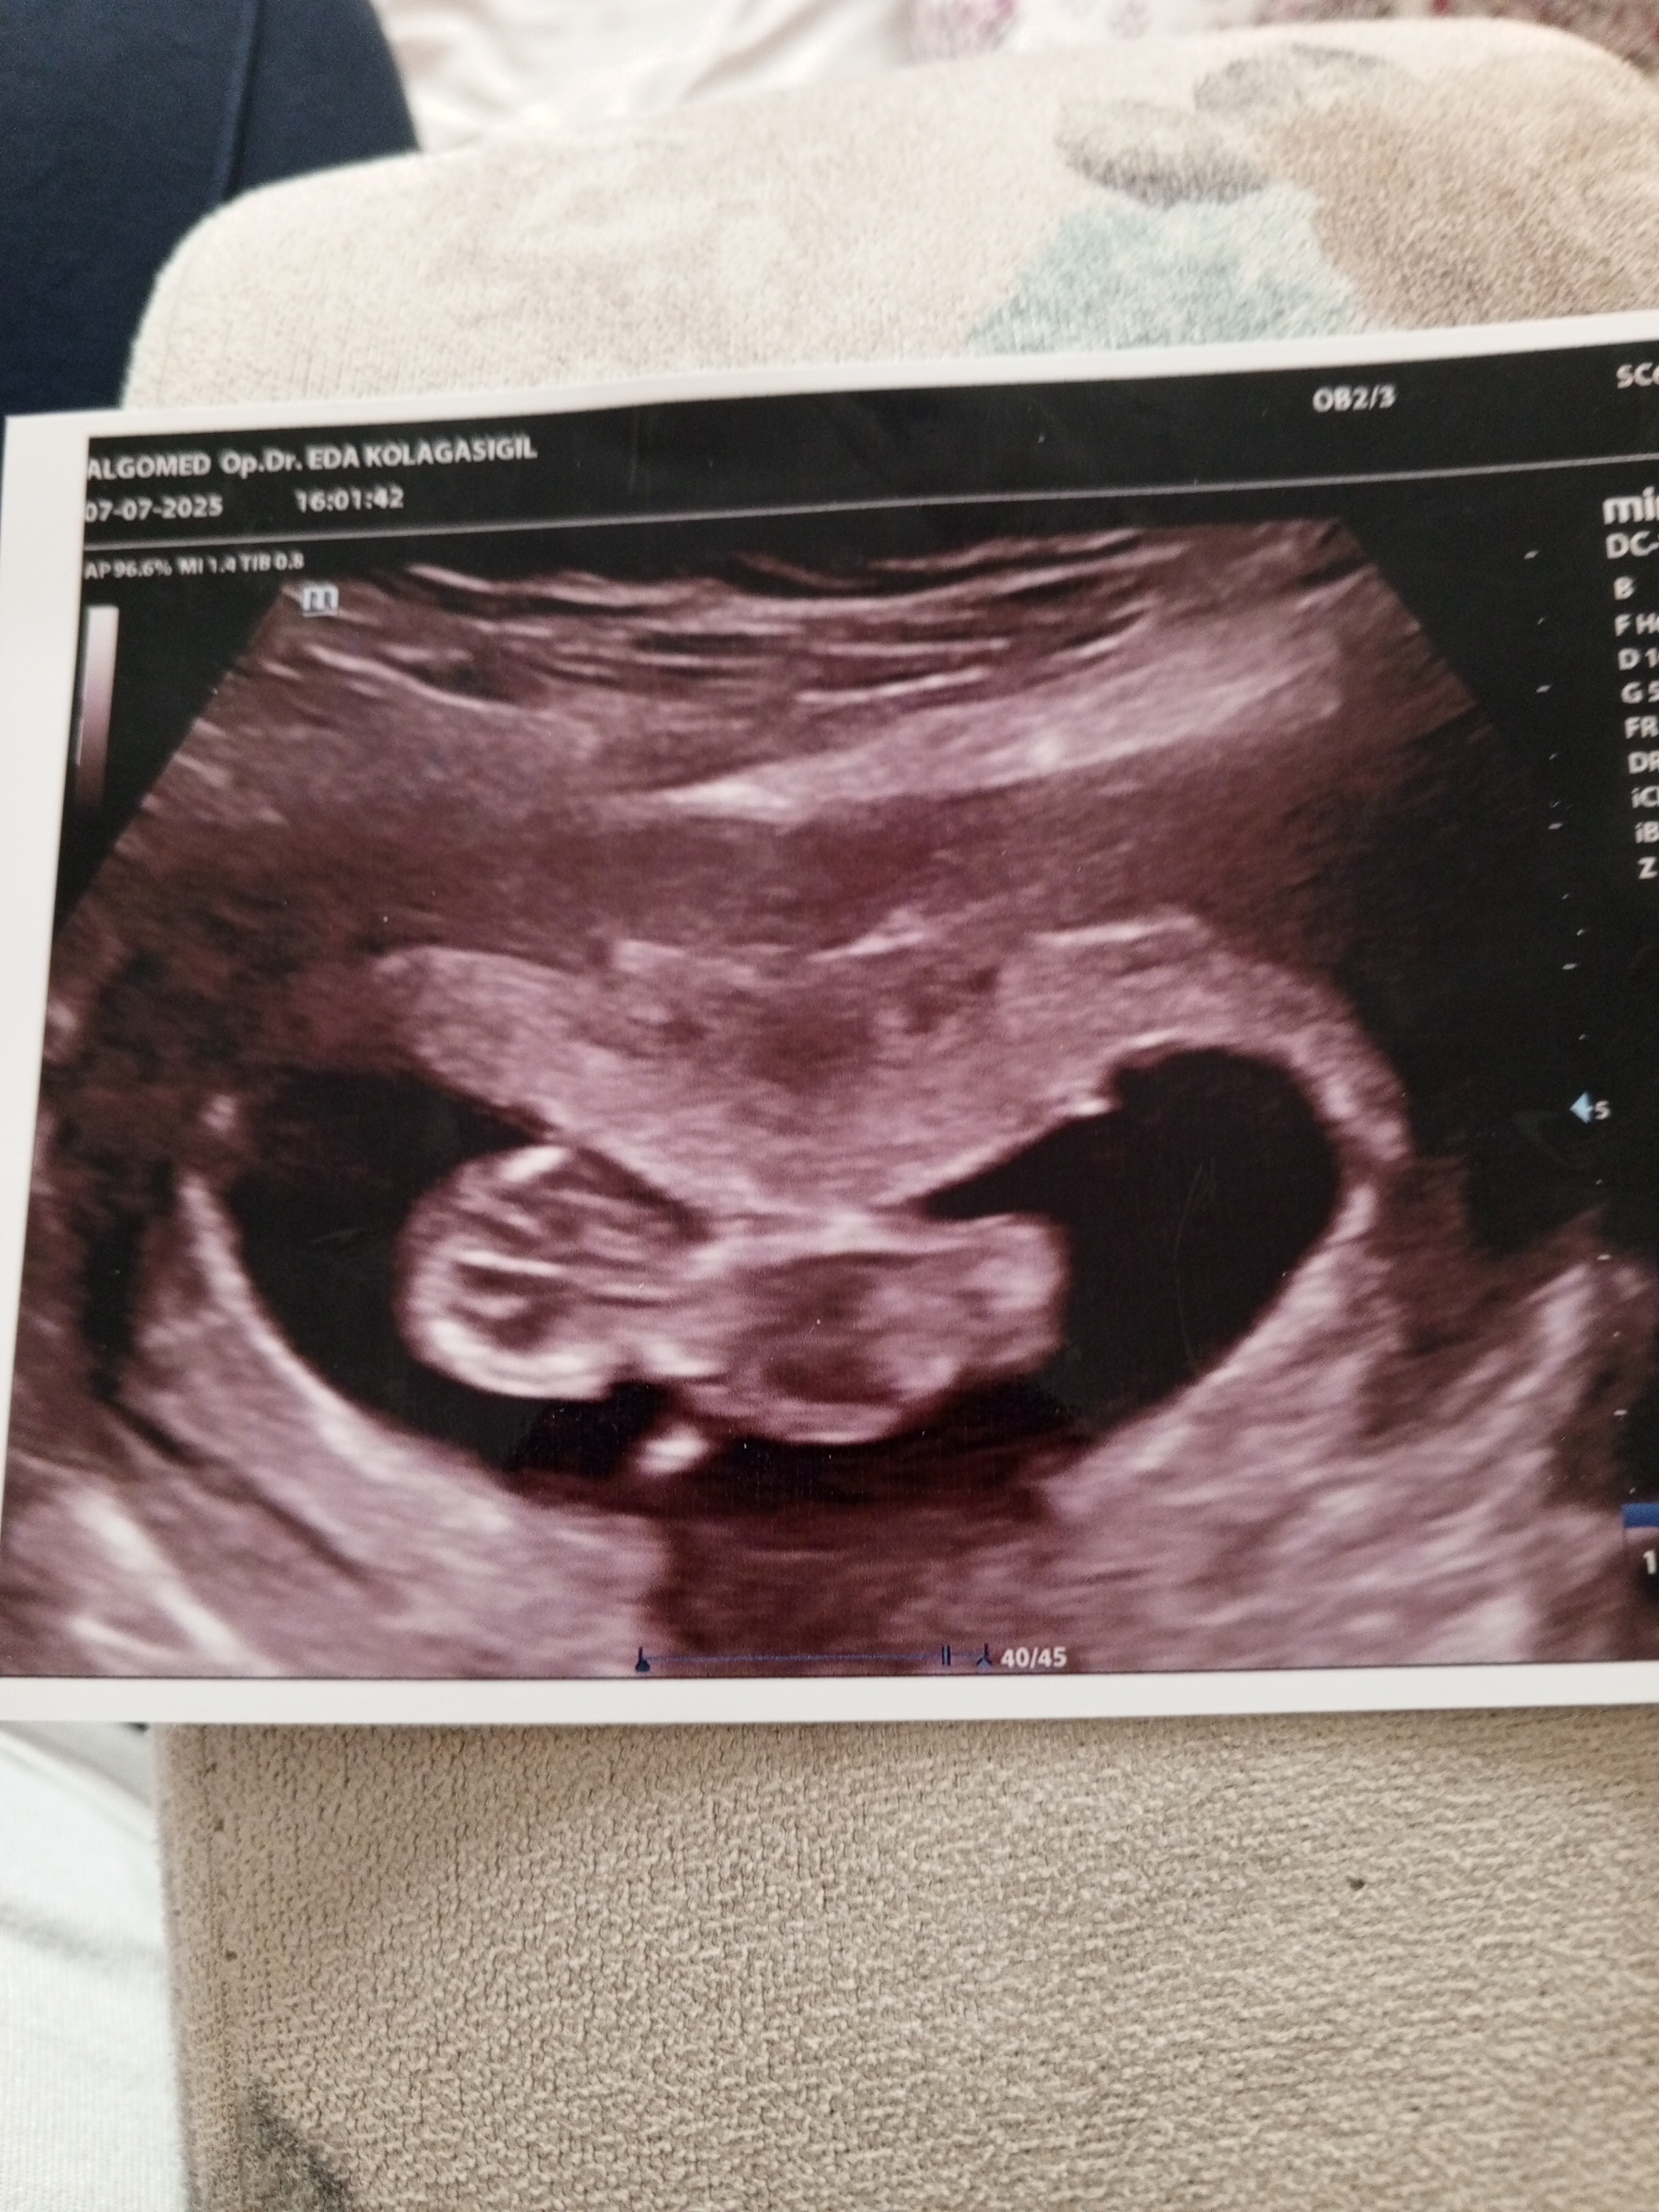

Ben kendi bebeğimin cinsiyetini nub teorisine göre tahmin etmiştim ama sizinki çok minik 🥰 2 hafta sonra olsaydı belki anlaşılırdı. Şu görünen kemik düz olduğunda kız, yukarı doğru eğik olduğunda erkek diyorlar